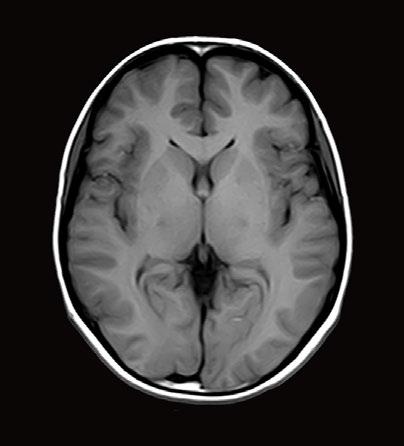

VISIONS SPECIAL // 37 © 2020 CANON MEDICAL SYSTEMS // MREU200039

Figure 2, Axial MRIs of the brain. Left: T1-weighted image (short TE and TR). Right: T2-weighted image (long TE and TR). Figure 3, Olea Nova + software. Top row: MP2RAGE images from which the T1-map is calculated and FSE mEcho images used to calculate the T2-map. Bottom row: Two synthetic images with different imaging parameters.

Canon Medical MR systems require two sequences to be able to calculate T1 and T2 relaxation times. To measure the T2-relaxation time, we use a 2D FSE mEcho (2D Fast Spin Echo Multi-Echo) sequence. This sequence acquires the signal multiple times after an excitation pulse (illustrated by dots in the T2-relaxation graph in Figure 1). The longer the time between the excitation and the signal acquisition (TE), the smaller the transverse magnetization becomes. This is an exponential process and the Olea software fits the data points to obtain the T2-relaxation time (Figure 3 – top right).

For the computation of the T1 relaxation time, we use a MP2RAGE sequence (Magnetization Prepared 2 RApid Gradient Echo). This sequence starts with inverting the longitudinal magnetization of all tissues and samples the regrowth of the magnetization at two different time points after this inversion. In the Olea software, the signal intensity at these two time points is fitted and the T1 relaxation time is determined at each voxel (Figure 3 – top middle). Before the fitting process of both the T1 and T2 relaxation times, motion correction is applied.